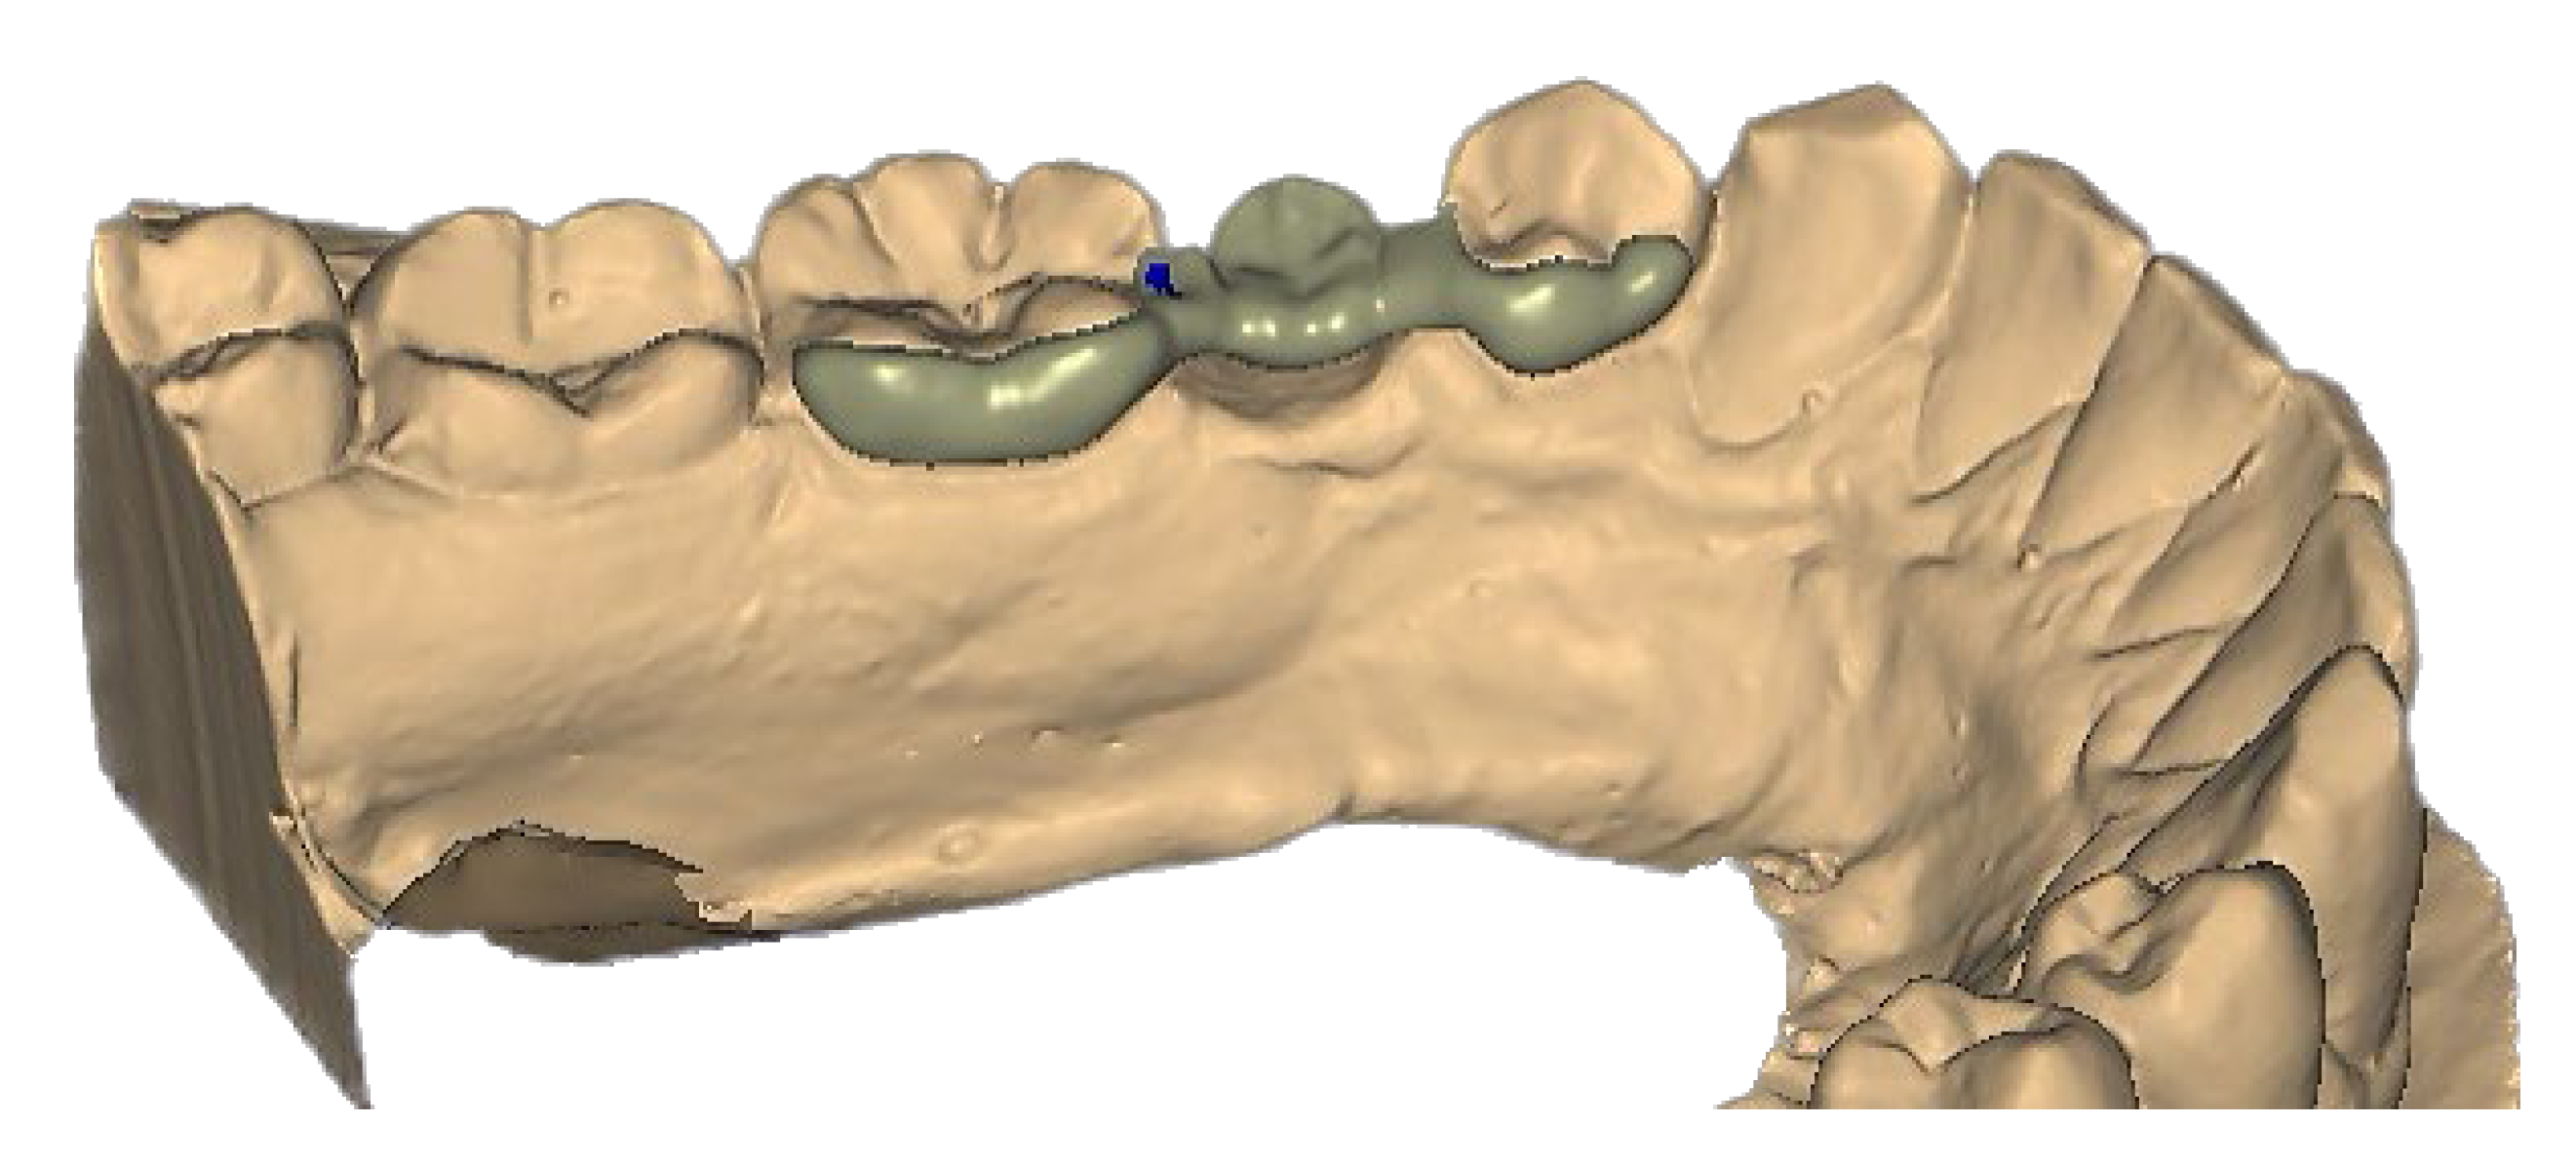

2.7. Resin-Bonded Prosthesis (RBP) Positioning